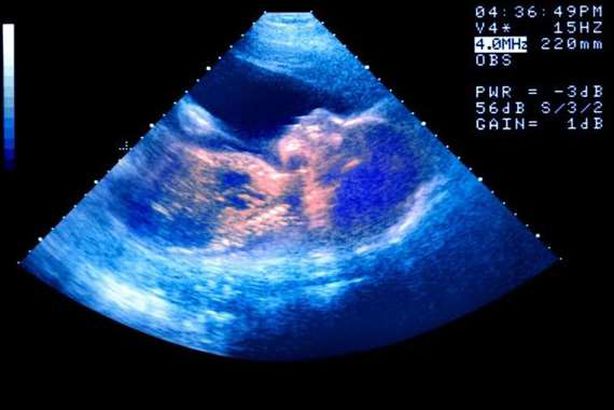

تحذير طبي: «كورونا» يهدد عمليات التلقيح الصناعي

حذرت الجمعية الأوروبية لعلم التكاثر البشري والأجنة (ESHRE )، من إجراء عمليات التلقيح الصناعي في هذه الآونة، في ظل مخاوف من تأثيرات سلبية محتملة لفيروس كورونا على السيدات خلال فترة الحمل.